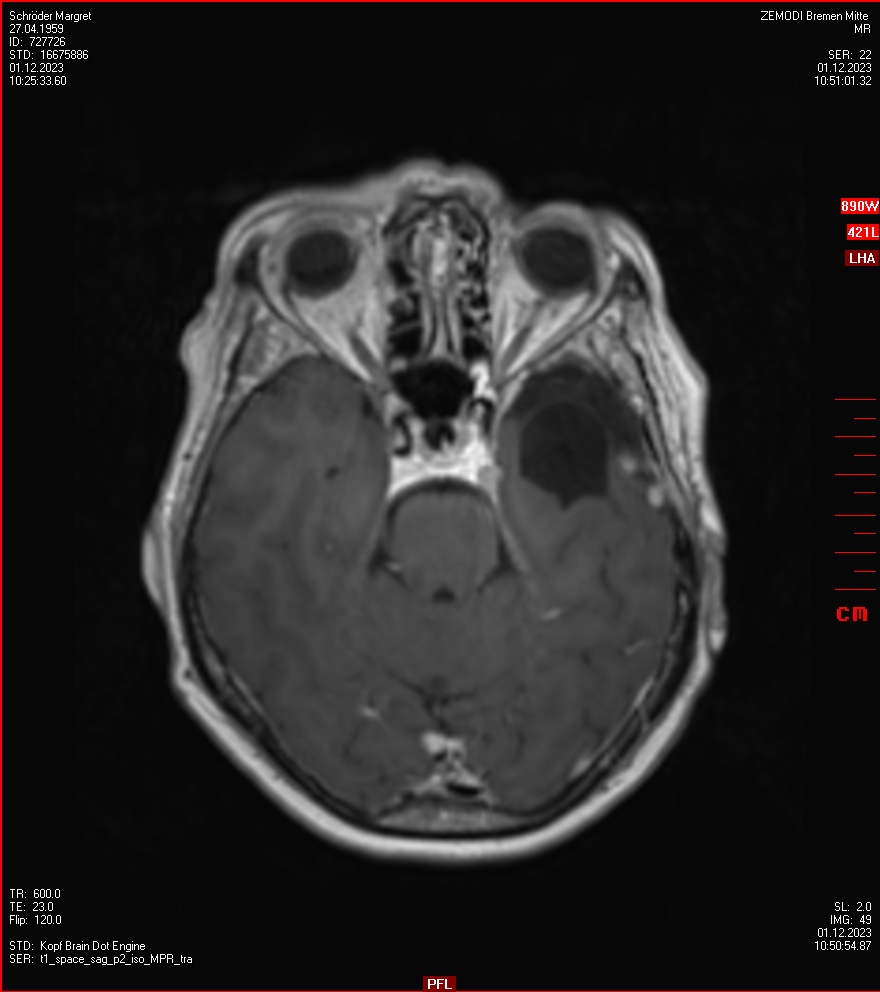

Zum Vergleich nun auch die Bilder vom 1.12.2023:

Ich denke, in den letzen 12 Monaten sind da ein paar Rezidive gewachsen,  vor 12 Monaten waren sie auch schon zu erkennen - vorher noch nicht. Nun hoffe ich auf den Rat des Spezialisten. Hoffendlich kann man etwas machen.